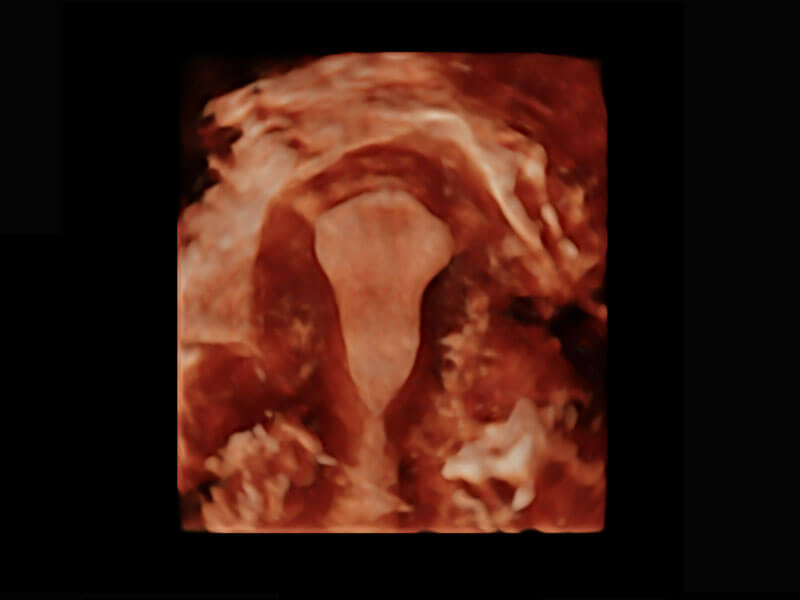

盆底超声

P60为盆底超声检查提供应用方案,多种腔内及腹部容积探头提供从二维、三维到四维的优异图像品质,实时快速三维容积数据获取,专业的测量工具包等人性化设计,为超声医生诊断提供有力保障。

S-Pelvic

能够简化盆底检查的操作流程,可在二维模式及三维成像模式下实现一键自动提取出标准切面、自动识别当前切面、自动测量,提升盆底检查的高效性,同时也能让青年医生快捷的获得准确的检查结果。